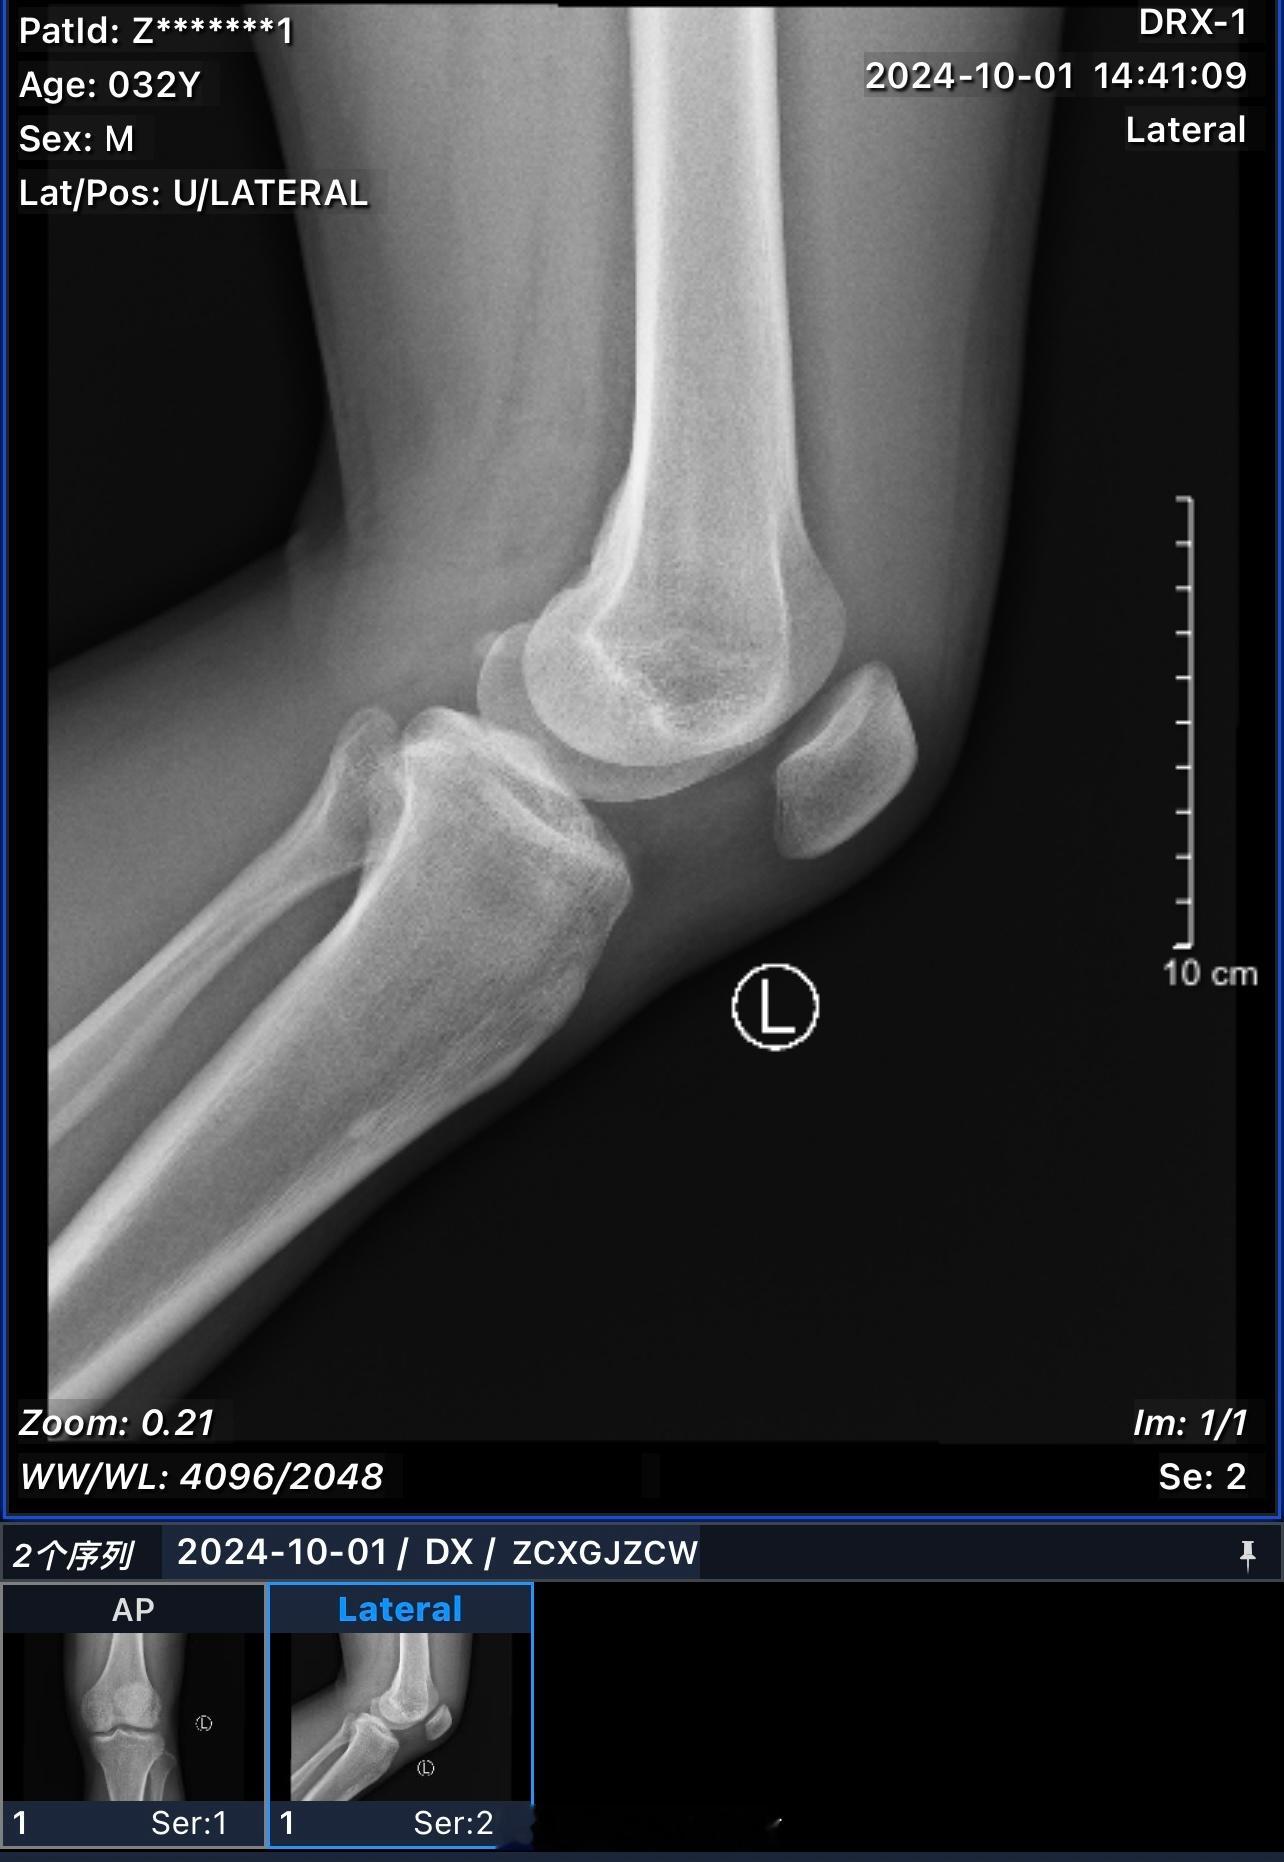

希望有惊无险,吓吓我就可以了。以后一定不逞强!已经30多岁了。欲速则不达,胜负欲

希望有惊无险,吓吓我就可以了。以后一定不逞强!已经30多岁了。欲速则不达,胜负欲也该降降了,希望兄弟们打球过程中,也要注意安全,不要强干,健康很重要 ​​​